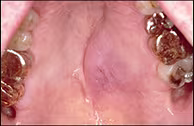

Non-Ulcerated Mass of the Hard Palate

A 66-year old white male presented with a raised lesion on the left hard palate. The patient had been aware of the lesion for approximately two weeks, and there was no history of recent or past trauma. The patient’s medical history was remarkable for a long history of epilepsy; however, the patient was not taking any prescription medication at the time of presentation.